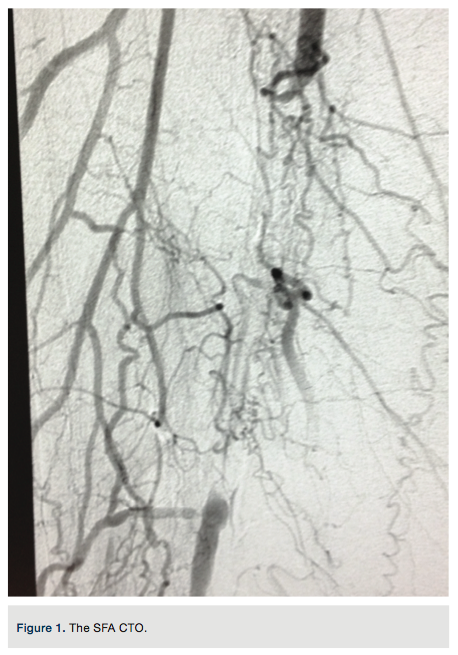

to gain purchase in the distal vessel within the true lumen. Placement was confirmed with a hand injection angiogram into the popliteal artery. There was no evidence of dissection. Routine debulking atherectomy was performed with the Jetstream Navitus 2.4 to 0.4 mm device with blades down (Figure 3) and blades up across the occluded segment (Figures 4-5) over the Spartacore wire. Balloon dilation was then performed with 5.0 x 80 mm and 6.0 x 80 mm Chocolate balloons (Trieme Medical)

(Figure6). There was an excellent angiographic result (Figure 7). The final angiographic image showed a -10% residual stenosis and brisk flow distally, with no dissection or extravasation of contrast. A pullback gradient assessment of femoral and popliteal artery to the proximal right SFA was performed and no gradient found. The Pinnacle Destination sheath was removed and a Perclose (Abbott Vascular) technique was used for left common femoral artery vascular access closure.